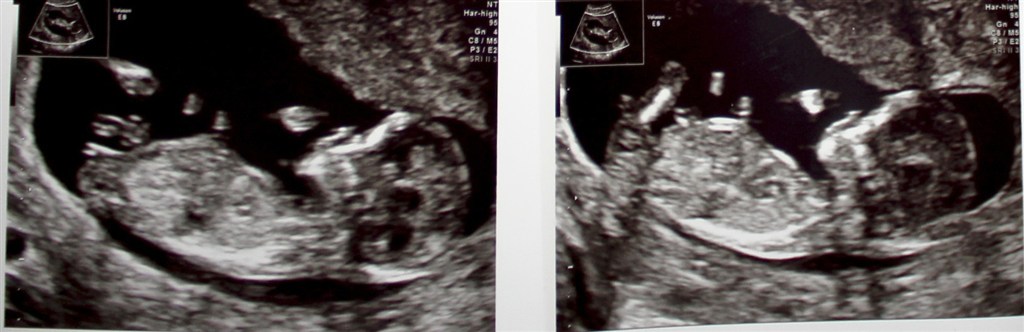

Det var dog heldigvis en fantastisk oplevelse. Vi fik hørt hjertelyd og set den lille ligge og sparke løs og vride sig. Oven i købet er jeg længere henne end først antaget, så terminen hedder nu d. 7. maj i stedet.

Det er fantastisk at se, hvor meget den lille har forandret sig siden vores TS d. 27. september. Til sammenligning kan I se billeder her: https://www.baby.dk/debat/193330pi1/ultralydsscanninger/tryghedsscanning-overstaaet.aspx